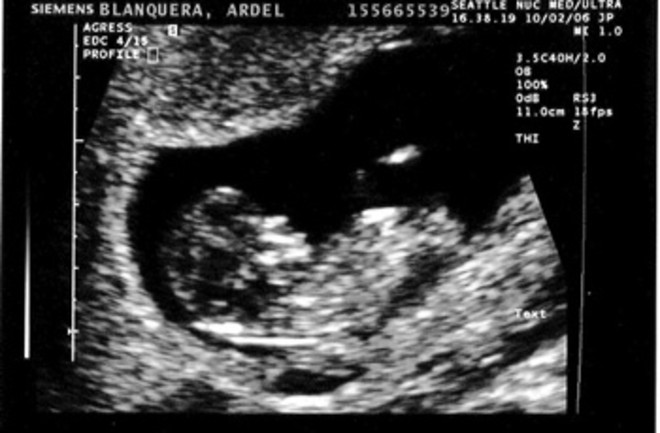

· Week 25 Ultrasound What It Would Look Like Now that you're 25 weeks pregnant, find out more about your baby's rapid brain development and sensory experiences in the womb By Kristen J Gough and · The Importance of the 12 Week Pregnant Ultrasound Scan The 12 week ultrasound is not just about gender reveal In fact, gender reveal is not even the main aspect of the scan The scan is conducted to examine whether the baby is growing as it should The foetus length, size of the internal organs and structures, development of skull etcetera · Now that you're weeks pregnant, you're halfway through your pregnancy — congratulations!

Week 25 Ultrasound What It Would Look Like Parents